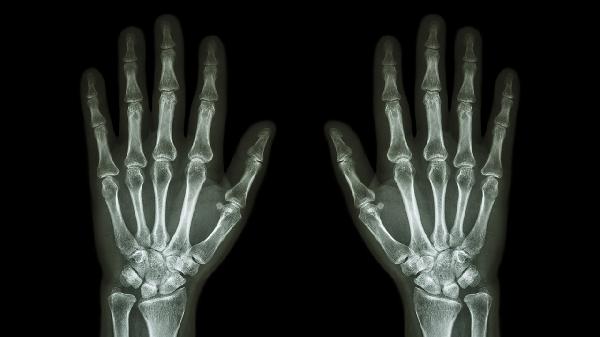

日常應(yīng)注意避免拇指過度用力或重復(fù)性動(dòng)作,使用電子設(shè)備時(shí)每隔30分鐘活動(dòng)手指。出現(xiàn)持續(xù)疼痛、關(guān)節(jié)變形或活動(dòng)受限時(shí)應(yīng)及時(shí)就診骨科或風(fēng)濕免疫科,通過X線、超聲等檢查明確診斷。寒冷季節(jié)注意手部保暖,可適當(dāng)熱敷促進(jìn)血液循環(huán)。